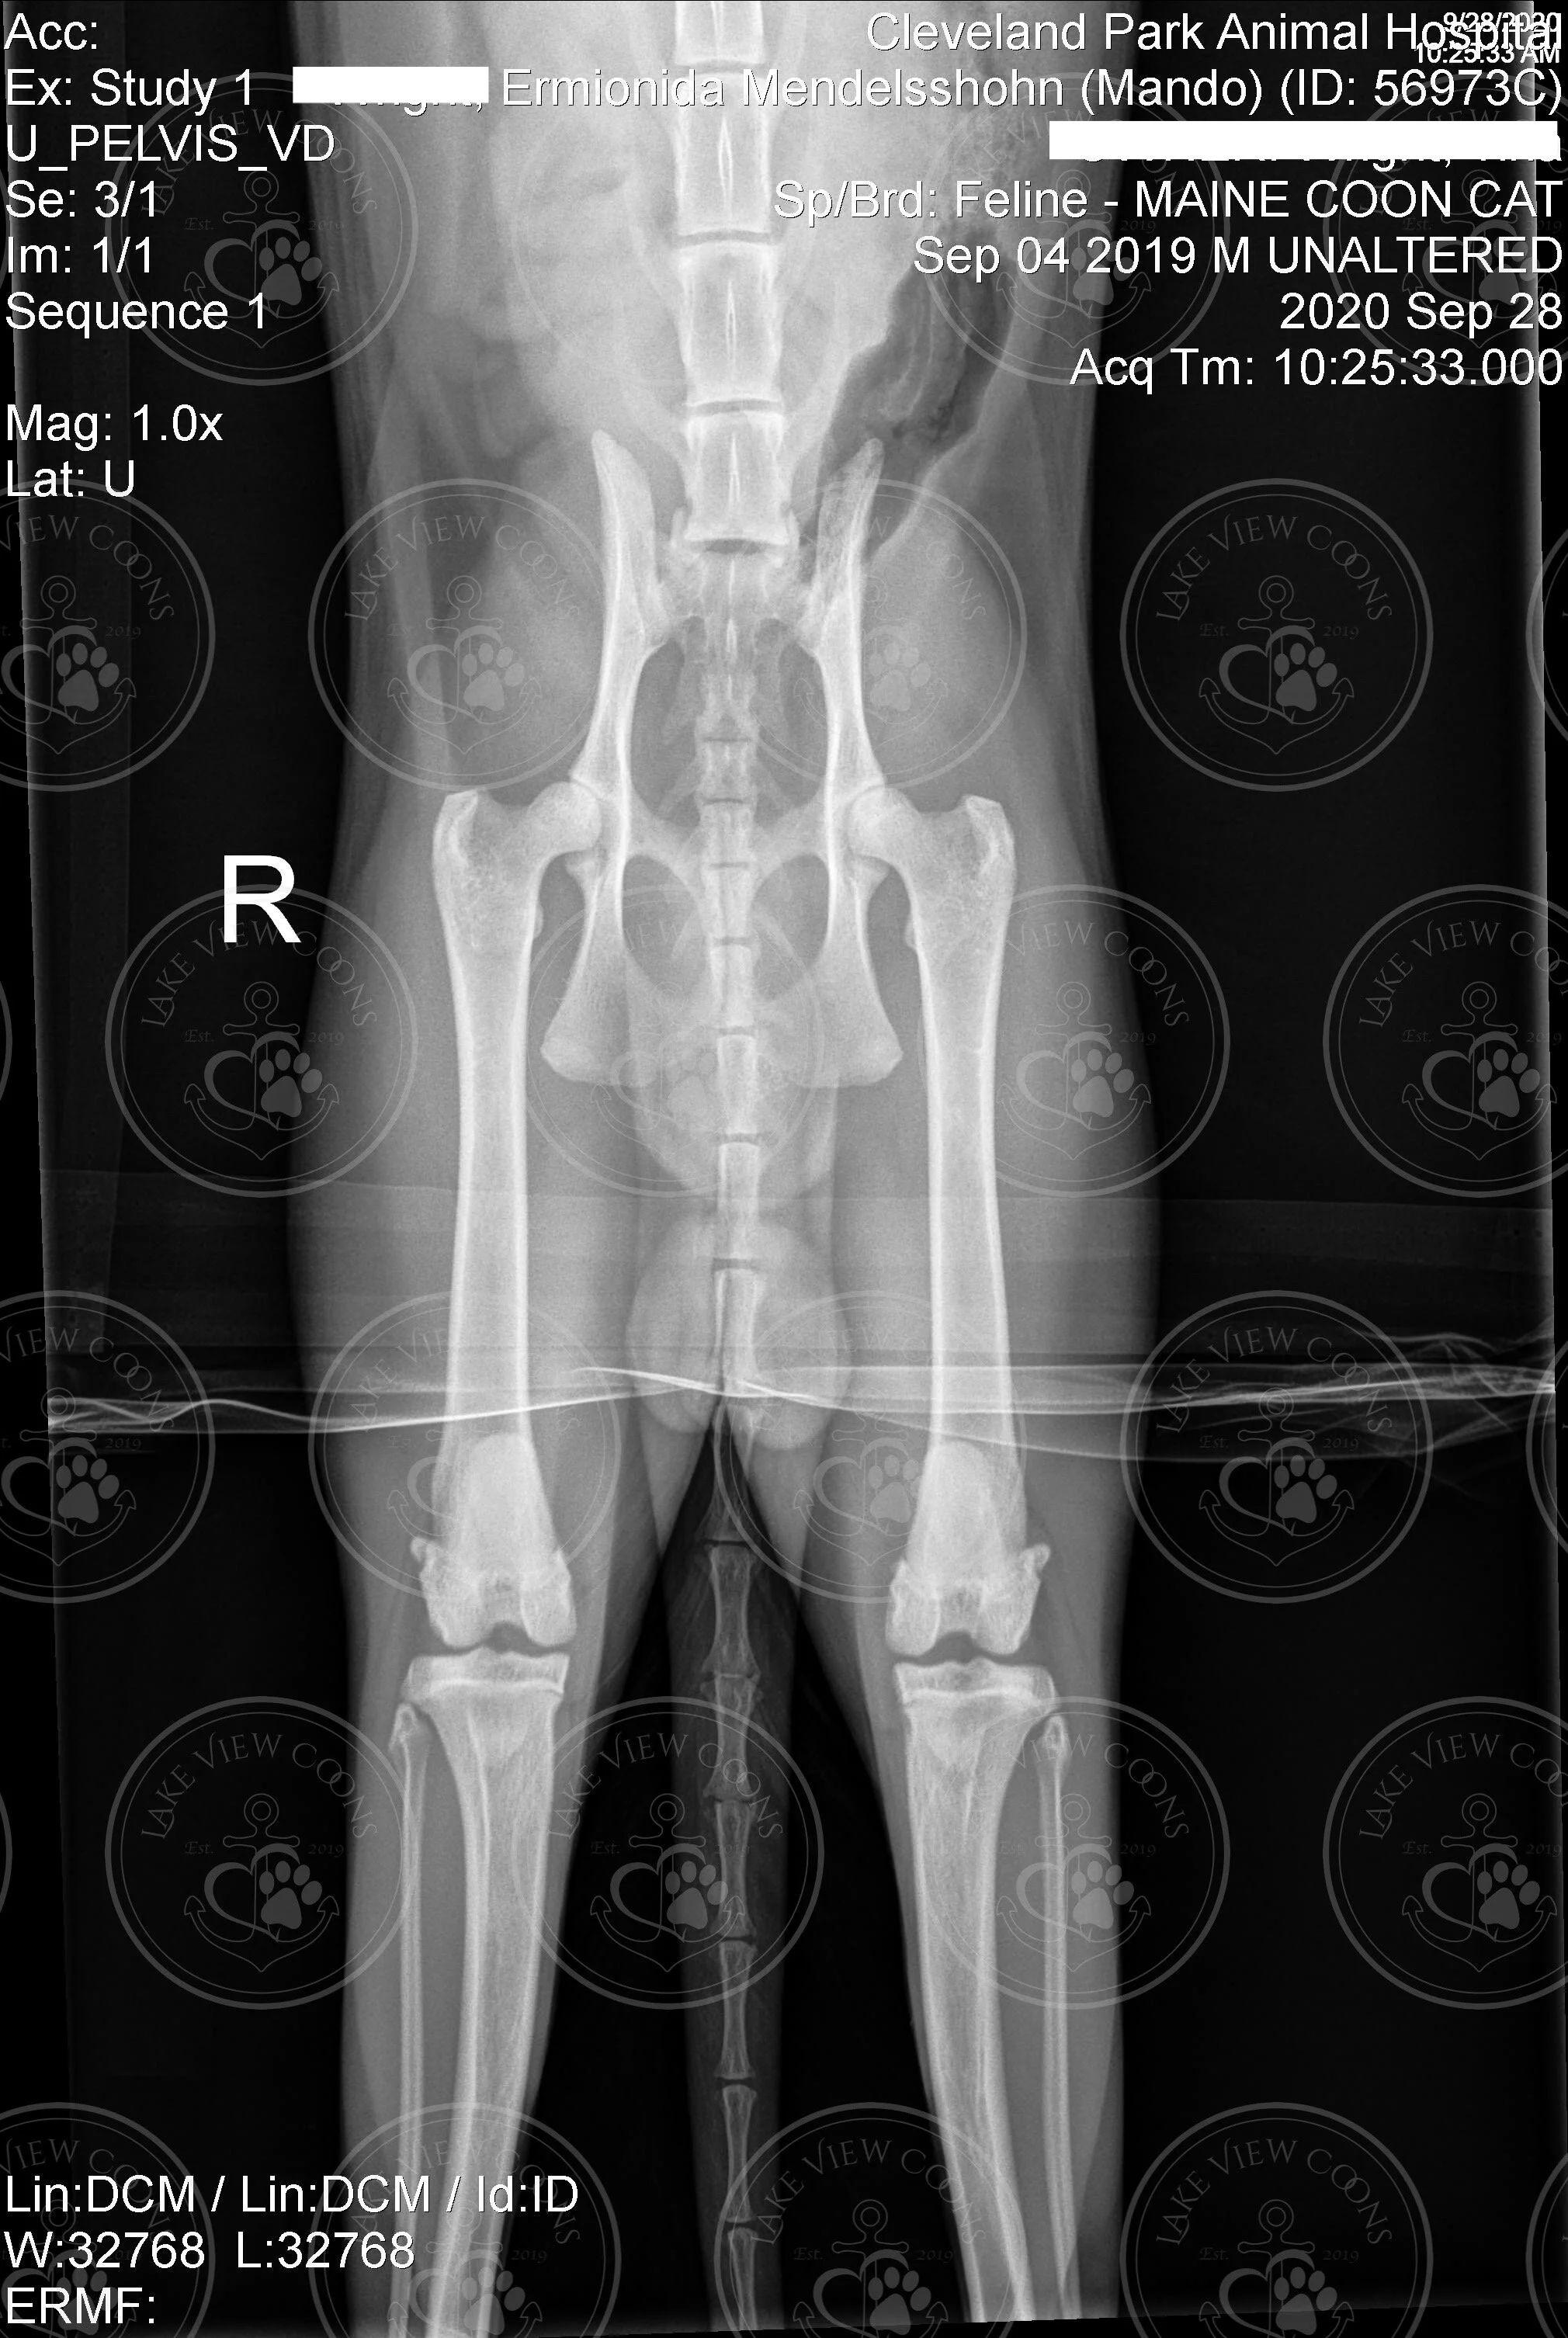

Ermionida Mendelssohn of Lake View Coons

Heart Echo & Hip X-Ray Results